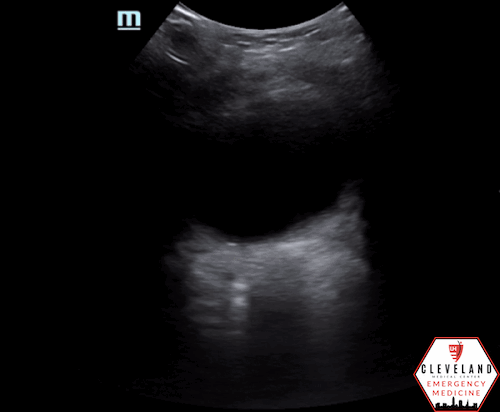

Given physical exam findings there was concern for imperforate hymen or other GU pathology decreasing communication between the uterus and external vaginal surface.  Point-of-care ultrasound was performed at this point and confirmed backup of blood in vaginal vault (hematocolpos) and a small amount of fluid in the uterus (hematometra), concerning for imperforate hymen

Findings suggestive of imperforate hymen: dilated and fluid-filled vagina (hematocolpos) +/- uterus (hematometra) - both seen in this patient’s case. Note that this fluid is well-circumscribed, unlike free fluid which usually has sharper/irregular edges.